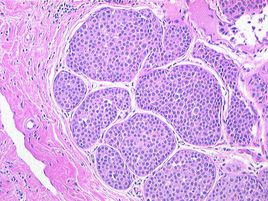

乳腺癌是女性最常見的惡性腫瘤之一,而乳腺導(dǎo)管癌則是乳腺癌最常見的病理類型,可占所有乳腺癌患者的70%左右。乳腺導(dǎo)管癌一旦發(fā)生轉(zhuǎn)移即發(fā)生進(jìn)展,其預(yù)后變得明顯惡化,中位生存時間僅為15~30個月。